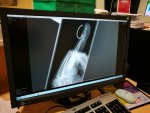

jeez geezer that is well in ,and bloody painful too .have done it a few times myself but with a lot smaller hooks than that boat anchor you carp heads use.